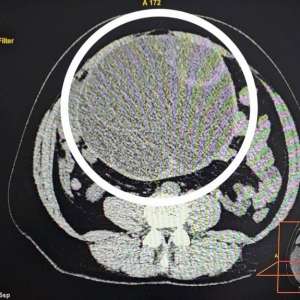

🤰 У жительницы Пензенской области нашли опухоль, соизмеримую с девятимесячным животом

Врачи из МСЧ №59 спасли жизнь молодой жительнице Заречного. Девушка из закрытого города в августе 2023 года заметила увеличение живота, но не придала этому значения, списав все на избыточный вес и неправильное питание. Только когда возникли сильные боли в животе, она обратилась к специалистам. Компьютерная томография выявила опухоль, которая занимала практически всю брюшную полость.

👨⚕ Врачи оперативно удалили образование, которое оказалось доброкачественным.